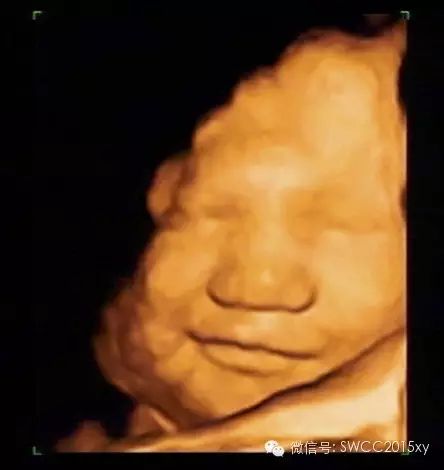

看我皱了一下眉,哦原来我是中国的宝宝,我不是西方的亚当,原来都是妈妈缺钙引起的。因此我们在判断胎儿是否缺钙,不仅仅是看胎儿的长骨的钙化程度和双顶径与股骨的比值,还可以利用现代先进的医学来判断,四维彩超的透明模式来看胎儿的肋骨发育提供更加准确、全面、科学的诊断依据,为减少先天性佝偻病做出应有的贡献。所以准妈妈一定要注意营养、规律、全程、有效补钙哦。